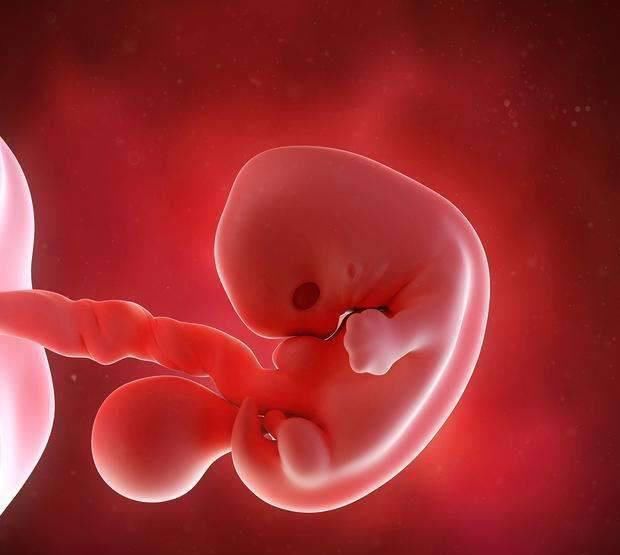

怀孕5周时,胚胎开始变身,分化成内、中、外三个胚层,不同的胚层将来分化成不同的结构或者器官,其中中胚层分化成循环系统,心脏开始成形,并且有了搏动,每分钟搏动70次。但是只有6mm,太微小,B超不容易判断。

怀孕6周时,胚胎像松子仁一样大,各个器官和四肢有了一定的雏形,血液循环系统的器官原型出现。胚胎蜷缩着,看上去就像一个“C”字。这个阶段在医学上成为“胚芽”,他不是胚胎的芽,就是指的整个胚胎。

怀孕7周时,心脏已经划分成左心房和右心室,开始有规律的跳动,每分钟跳150次,开始有血液循环。